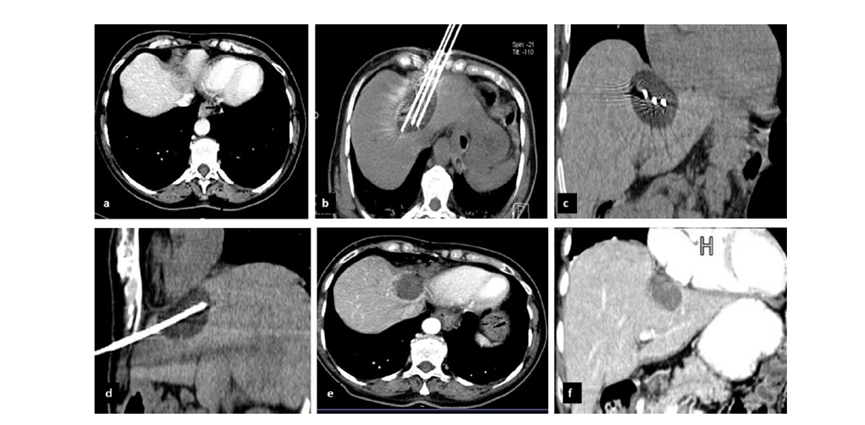

(A)動脈期 MRI 顯示膽囊附近有外周增強病變(箭頭)。

(B)手術過程中 CT 顯示冷凍探針位于病灶內。

(C)消融后,術后 1 個月CT 顯示完全消融(箭頭)。

(A)動脈期CT圖像顯示有一個包膜下結節(箭頭)。(C) 在手術過程中的CT顯示一個冷凍探針位于病灶內。隨訪時間中位數為7個月(范圍:3-12個月),隨訪期間患者無局部腫瘤進展或死亡。

(A)門靜脈期 CT 圖像顯示膽囊附近有病變(箭頭)。(D)消融手術后 1 個月CT 顯示完全消融。

CT引導的冷凍消融